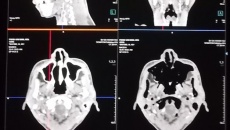

Phình động mạch được chẩn đoán tại bệnh viện bằng các xét nghiệm hình ảnh chuyên biệt như chụp cộng hưởng từ mạch máu (MRA), chụp cắt lớp vi tính mạch máu (CTA) hoặc chụp mạch số hóa xóa nền, giúp bác sĩ có được hình ảnh chi tiết về não và mạch máu.